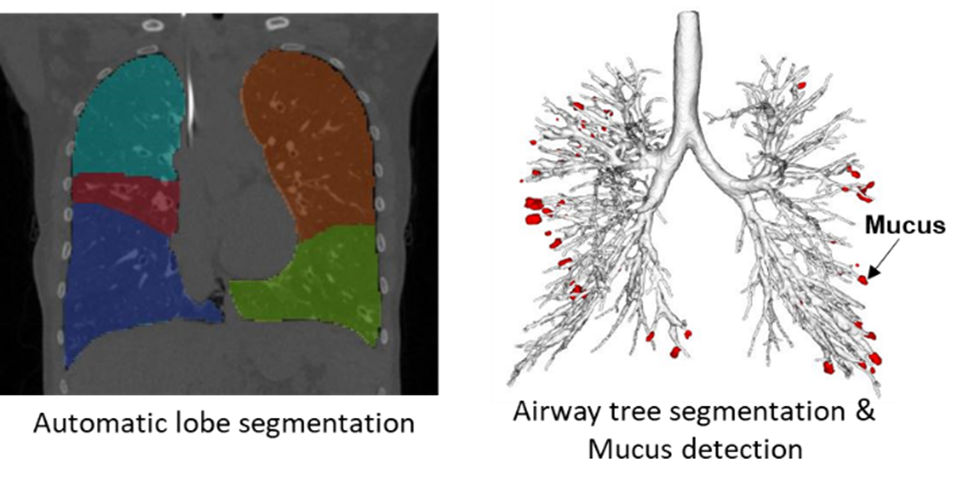

LungAnalysis has been working towards developing automated tools to quantify lung structural abnormalities. The lab has ongoing collaborations with Thirona B.V. (Nijmegen), a Dutch company specializing in cutting-edge artificial intelligence strategies for quantitative lung imaging. Together, LungAnalysis and Thirona co-developed a fully automated, sensitive system to measure bronchial widening, bronchial thickening, mucus plugging, and trapped air on chest CT. The algorithm has been integrated into Thirona’s certified software platform, LungQTM, which is installed on the virtual platform DRE at LungAnalysis, Erasmus MC. Current work on the validation of the automated tools is ongoing in a wide range of lung diseases, including CF.